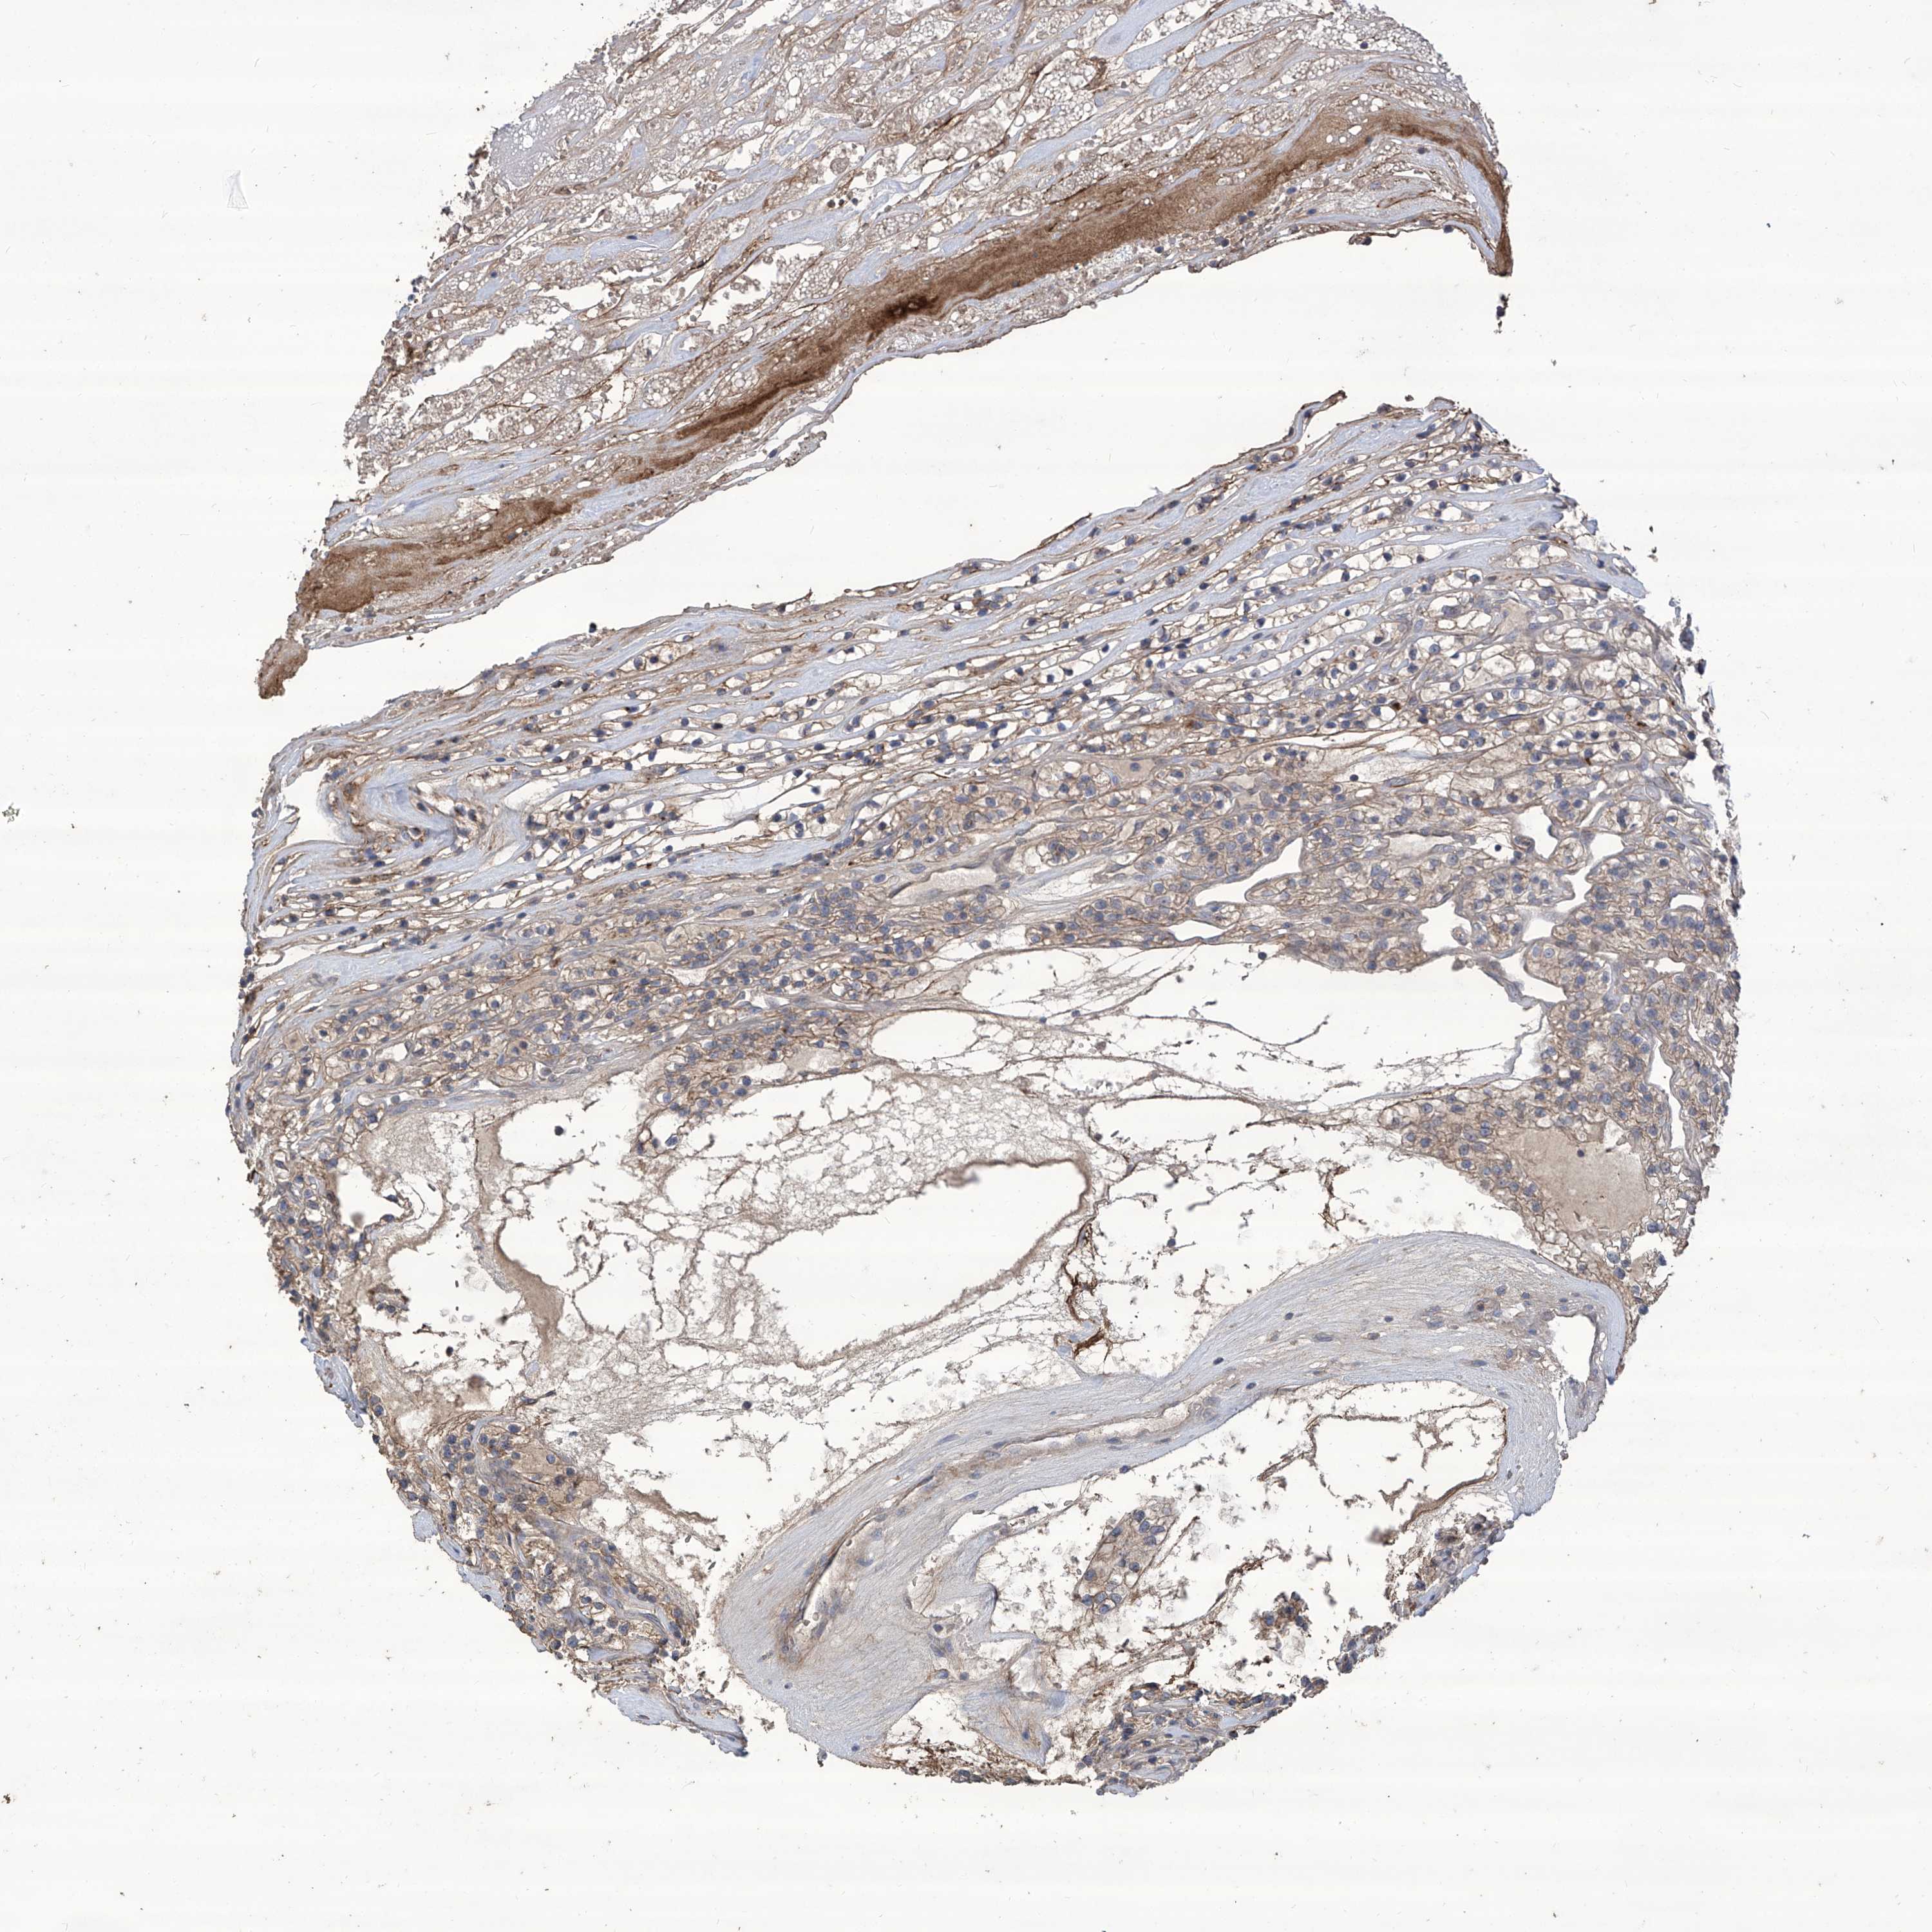

KIDNEY RENAL CLEAR CELL CARCINOMA (VALIDATION) - Interactive survival scatter ploti

The Survival Scatter plot shows the clinical status (i.e. dead or alive) for all individuals in the patient cohort, based on the same data that underlies the corresponding Kaplan-Meier plots. Patients that are alive at last time for follow-up are shown in blue and patients who have died during the study are shown in red.

The x-axis shows the expression levels (FPKM) of the investigated gene in the tumor tissue at the time of diagnosis. The y-axis shows the follow-up time after diagnosis (years). Both axes are complimented with kernel density curves demonstrating the data density over the axes. The top density plot shows the expression levels (FPKM) distribution among dead (red) and alive patients (blue). The right density plot shows the data density of the survived years of dead patients with high and low expression levels respectively, stratified using the cutoff indicated by the vertical dashed line through the Survival Scatter plot. This cutoff is automatically defined based on the FPKM cutoff that minimizes the p-score. The cutoff can be changed by dragging the vertical line or by entering a cutoff value in the square labeled "Current cut-off".

Under the Survival Scatter plot the p-score landscape (black curve; left axis) is shown together with dead median separation (red curve; right axis). Dead median separation is the difference in median mRNA expression between patients who have died with high and low expression, respectively. It is calculated as follows: median FPKM expression of dead patients with high expression - median FPKM expression of dead patients with low expression. This is intended to aid the user in visually exploring custom cutoffs and the associated p-scores and dead median separation.

Individual patient data is displayed and can be filtered by clicking on one or more of the category buttons on the top of the page. Categories describing expression level and patient information include: high, low, alive, dead, female, male and tumor stages. The scale of the x-axis can be toggled between linear and log-scale by clicking on the "x log" button. Mouse-over function shows TCGA ID, patient information and mRNA expression (FPKM) for each patient.

& Survival analysisi

Kaplan-Meier plots summarize results from analysis of correlation between mRNA expression level and patient survival. Patients were divided based on level of expression into one of the two groups "low" (under cut off) or "high" (over cut off). X-axis shows time for survival (years) and y-axis shows the probability of survival, where 1.0 corresponds to 100 percent.

TXNIP is not prognostic in Kidney Renal Clear Cell Carcinoma (validation)

Best expression cut offi

Based on the FPKM value of each gene, patients were classified into two groups and association between prognosis (survival) and gene expression (FPKM) was examined. The best expression cut-off refers the FPKM value that yields maximal difference with regard to survival between the two groups at the lowest log-rank P-value. Best expression cut-off was selected based on survival analysis .

When clicking on this number, the vertical dashed line indicating cut-off, the interactive survival plot, and the Kaplan-Meier curve will be adjusted to show results based on the best expression cut-off.

: 478.37

P scorei

Log-rank P value for Kaplan-Meier plot showing results from analysis of correlation between mRNA expression level and patient survival.

N/A

5-year survival highi

5-year survival for patients with higher expression than the expression cutoff.

For melanoma and glioma, 3-year survival is shown.

5-year survival lowi

5-year survival for patients with lower expression than the expression cutoff.

TCGA RNA samplesi

RNA-seq data is reported as average FPKM (number Fragments Per Kilobase of exon per Million reads), generated by the The Cancer Genome Atlas (TCGA) .

Normal distribution across the dataset is visualized with box plots, shown as median and 25th and 75th percentiles. Points are displayed as outliers if they are above or below 1.5 times the interquartile range. FPKM values of the individual samples are presented next to the box plot.

Average pTPM 691.0

Number of samples 100